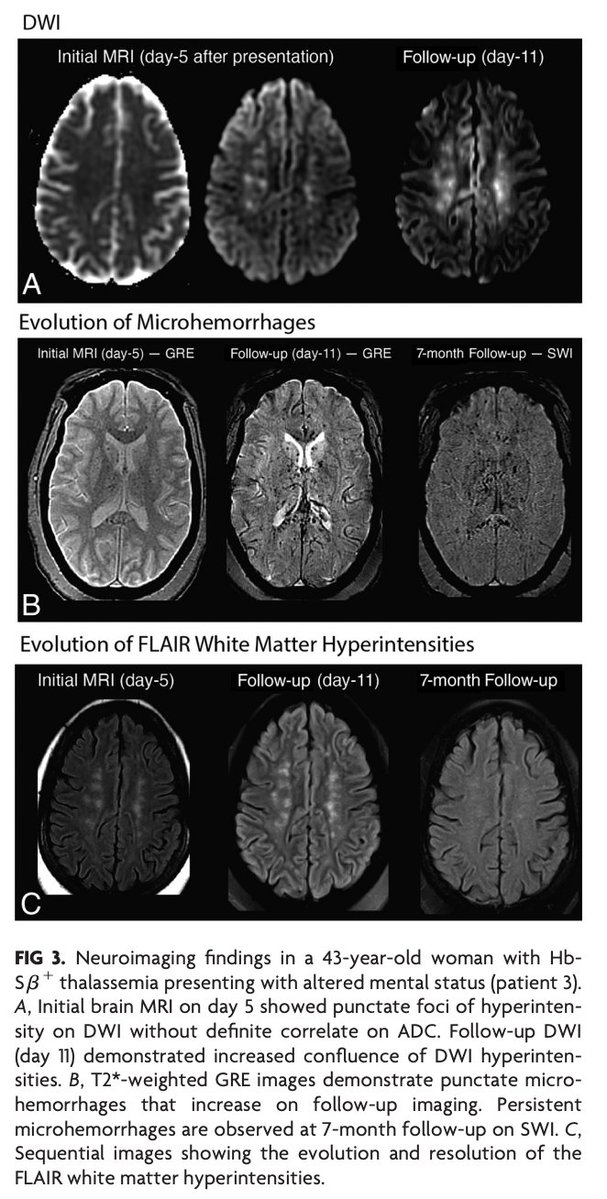

@Rshnzr @HosseiniHelia @zack4186 "CFE in sickle cell–related hemoglobinopathies is more common in complex hemoglobinopathies with otherwise milder disease course and is typically more fulminant compared with traumatic CFE. MRI findings follow a pattern with scattered foci of restricted diffusion, known as the

"Nontrauma-Associated Cerebral Fat Embolism Syndrome in Sickle Cell–Related Hemoglobinopathies: A Case Series and Systematic Review" https://t.co/mjcZ5AQXte

#FellowsJournalClub

@Rshnzr; @HosseiniHelia; @zack4186